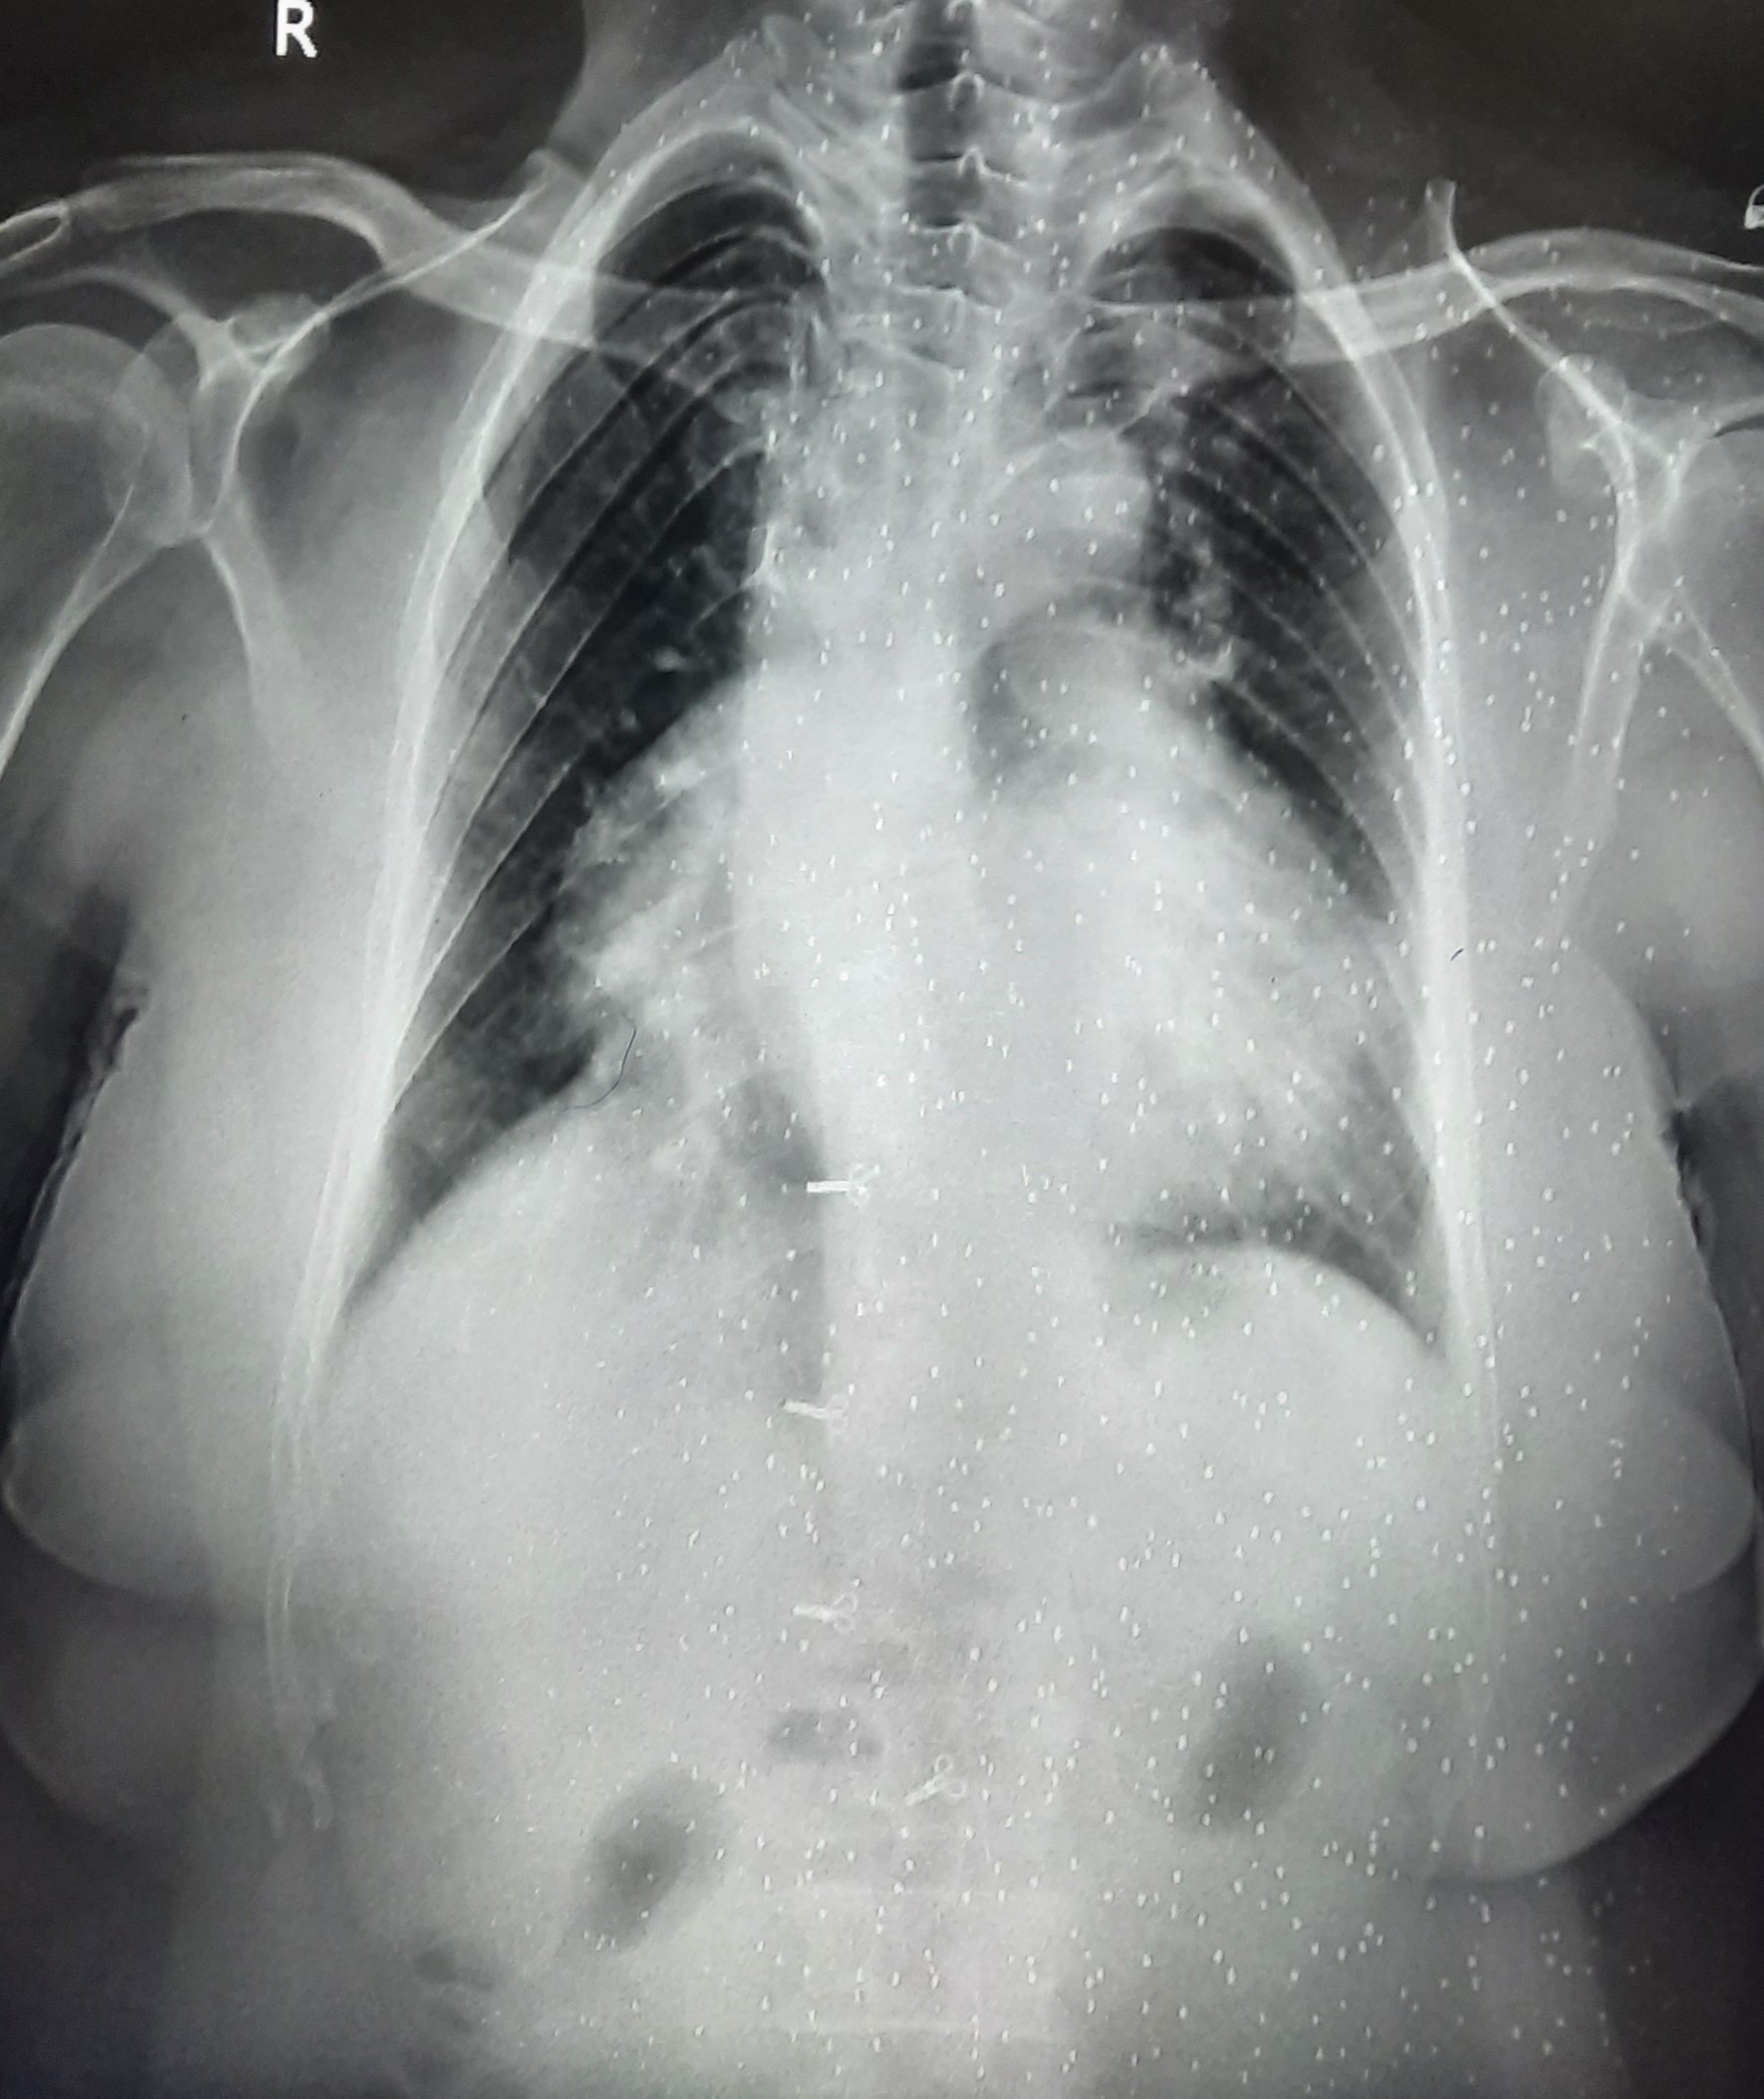

| 285 | IGGMC, Nagpur, Nagpur | P2 | 29-4187 | Kalpna Hatmode | Consent taken on Paper | 47 Yrs. |

Provisional Diag : Interstitial Lung Disease

Final Diag : ILD (Interstitial Lung Disease) |

Non-TB Case (Confirmed) | Abnormality visible on x-ray |